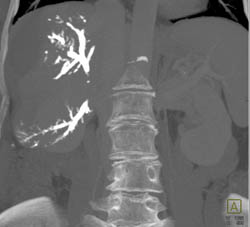

Fatty Liver